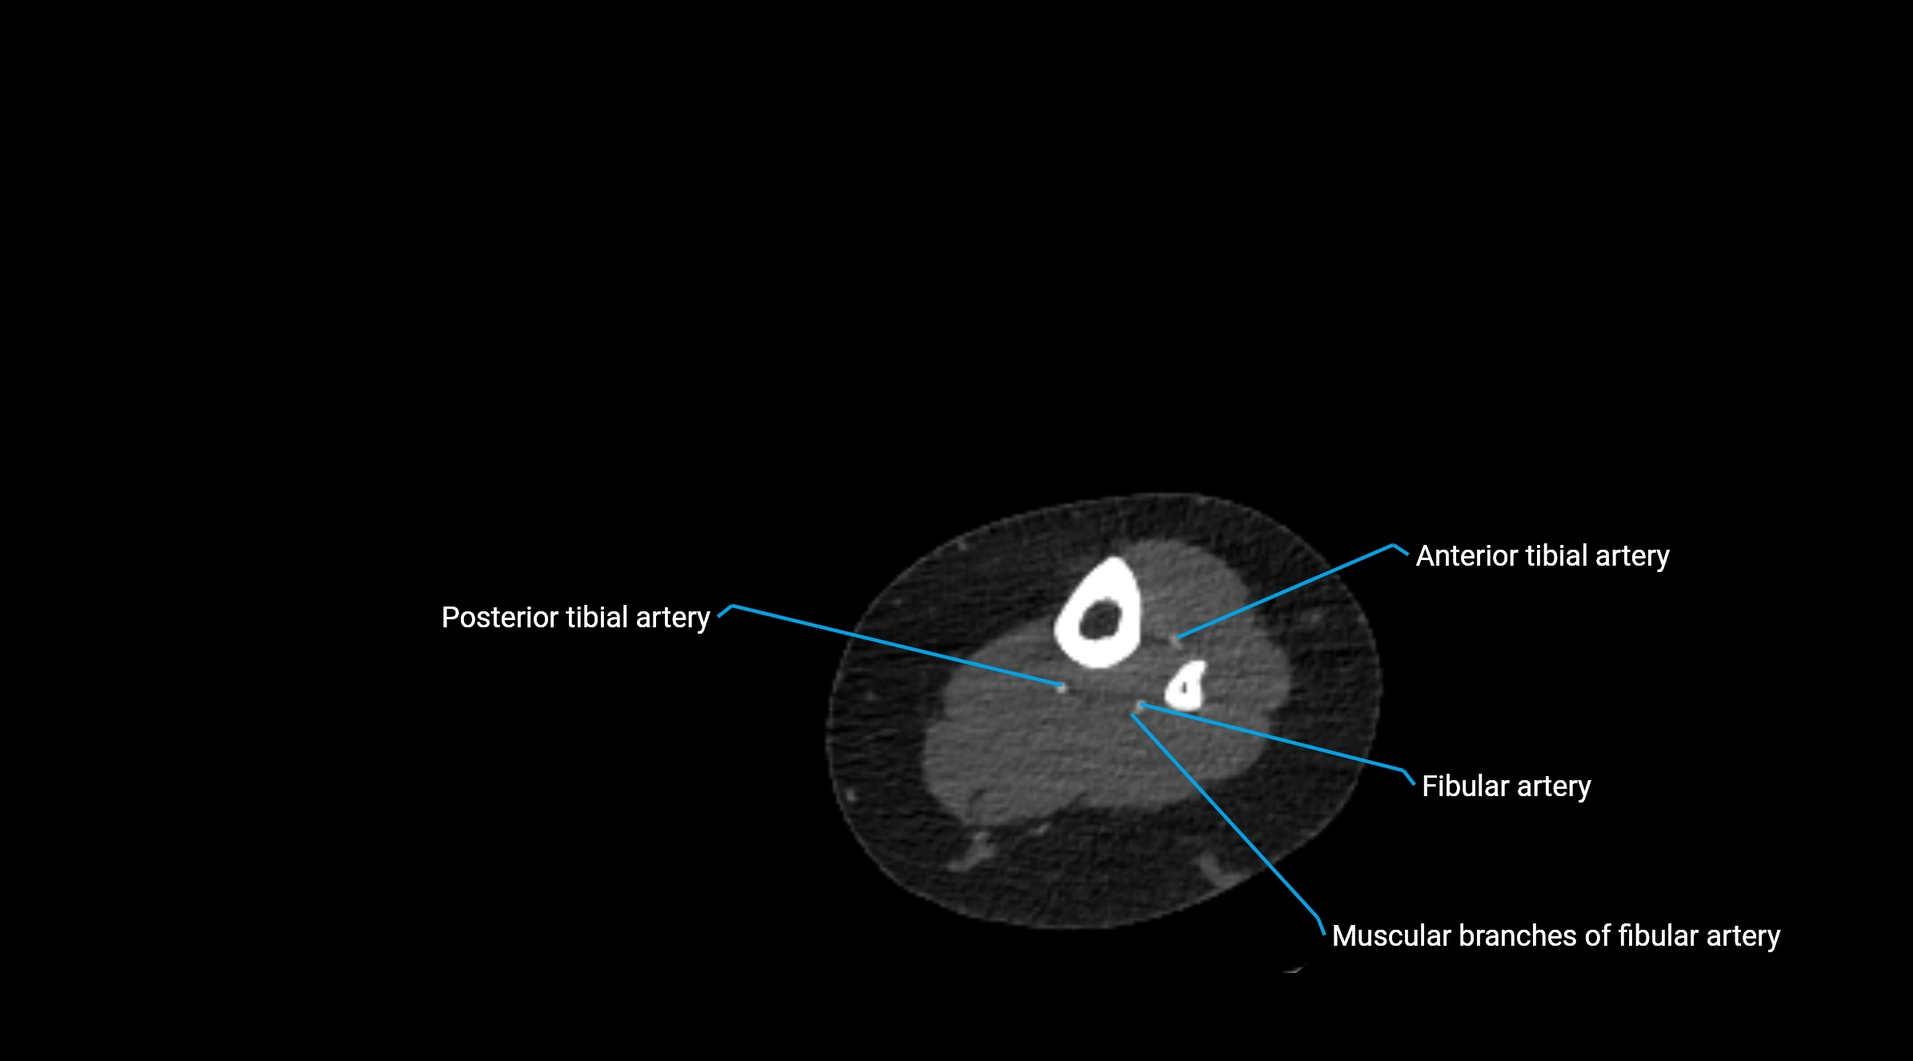

Contrast-enhanced CT (CTA):

• Gold standard for abdominal aortic imaging

• Provides excellent detail of lumen, wall, aneurysm, thrombus, and branch vessels

• Multiplanar and 3D reconstructions help in aneurysm measurement, stent graft planning, and dissection evaluation

• Detects acute rupture, traumatic injury, or occlusion with high sensitivity